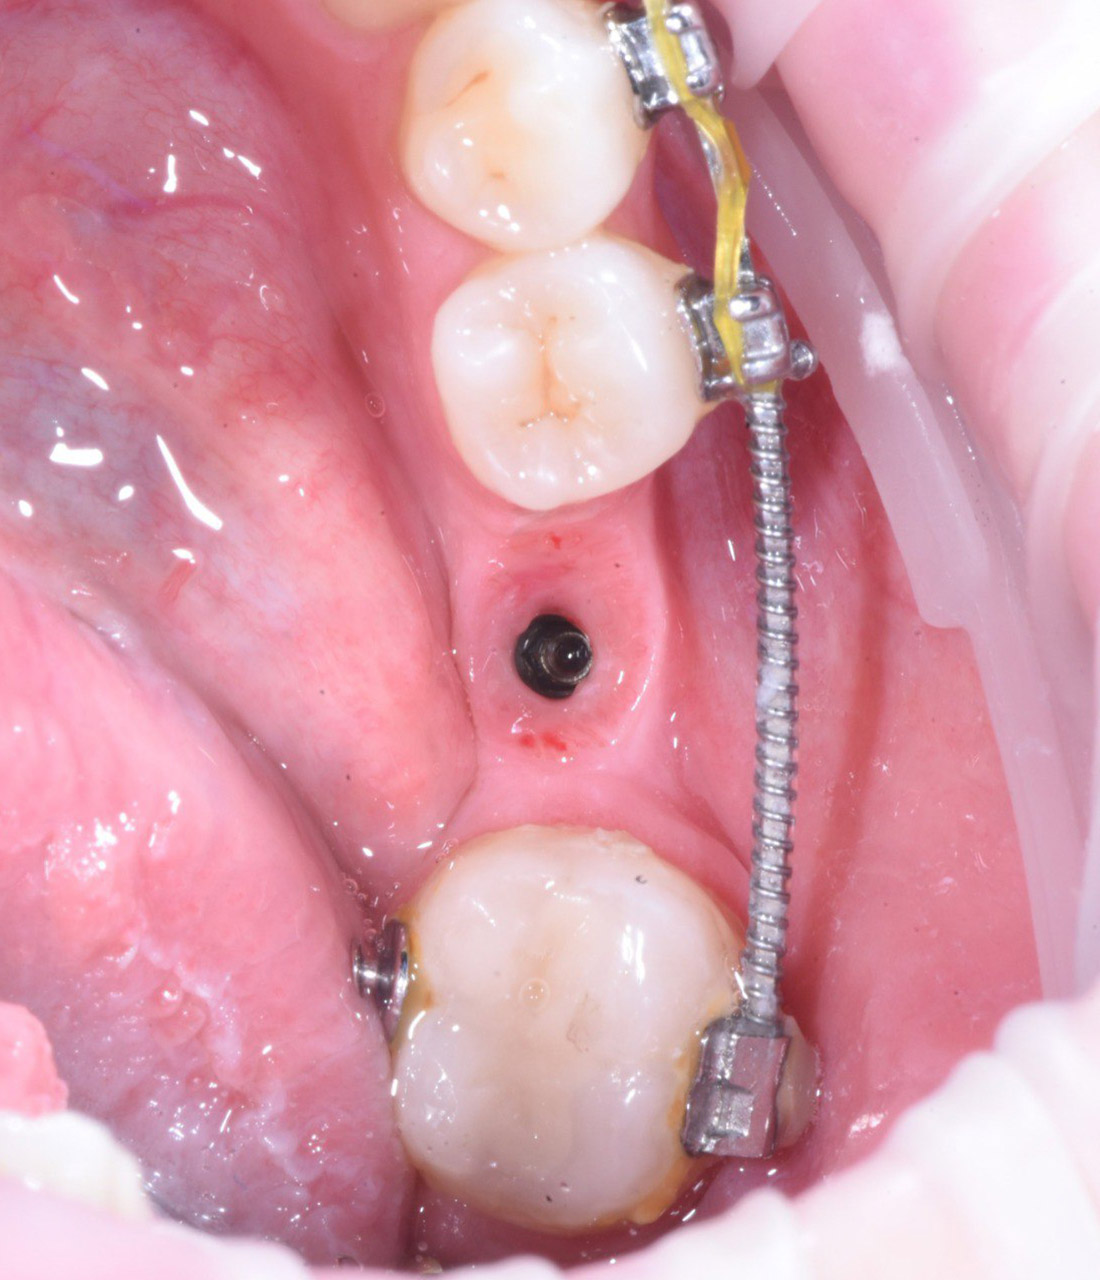

Имплантация нижнего моляра системой Osstem с протезированием циркониевой коронкой